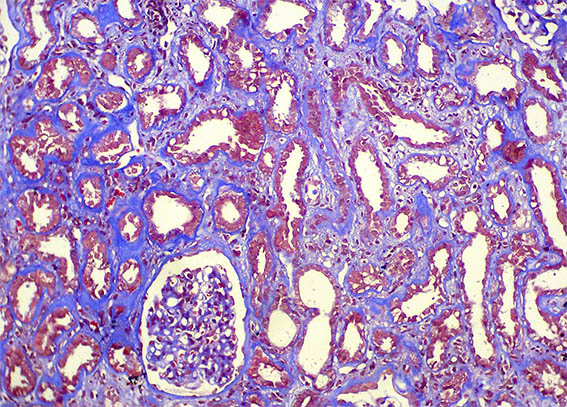

A renal allograft biopsy was done, see the images.

Figure 4. Masson's trichrome stain, X200.